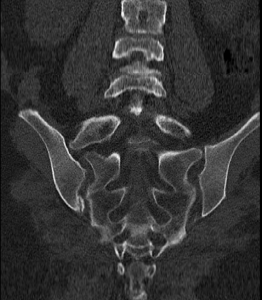

Tipo IIA según Clasificación de Castellvi

Clasificación de Castellvi para el síndrome de Bertolotti

La clasificación de Castellvi se utiliza para categorizar las diferentes manifestaciones de las vértebras transicionales que pueden relacionarse con el síndrome. Esta clasificación ayuda a sistematizar el diagnóstico y a definir un enfoque terapéutico adecuado.

Tipo I

El Tipo I se caracteriza por la presencia de procesos transversos displásicos, que son significativamente más largos y pueden medir al menos 19 mm. Esta anomalía puede influir en la biomecánica de la columna y contribuir al dolor lumbar.

Tipo II

En el Tipo II, se observa una lumbarización o sacralización que genera una diartrosis con el sacro. Esta articulación adicional puede ser un foco de dolor, ya que puede incrementar la carga sobre la región lumbosacra.

Tipo III

El Tipo III implica la fusión de la apófisis transversa con el sacro. Esta fusión puede limitar el rango de movimiento de la columna, predisponiendo al paciente a la aparición de dolor crónico.

Tipo IV

El Tipo IV combina las características de los tipos I y II, presentando tanto la displasia en la apófisis transversa como una diartrosis con el sacro. Esta combinación puede resultar en un dolor más complejo y en un manejo clínico más desafiante.

Imágenes radiológicas representativas de la Clasificación de Castellvi de las anomalías de transición lumbosacra. Tipo I: presencia de espolones óseos (a) unilaterales o (b) bilaterales. Tipo II: articulaciones accesorias (a) unilaterales o (b) bilaterales. Tipo III: fusión ósea completa (a) unilateral o (b) bilateral. Tipo IV: combinación de fusión ósea completa unilateral y articulación accesoria contralateral.